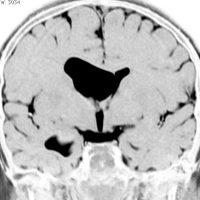

シルビウス裂くも膜のう胞,中頭蓋窩くも膜のう胞

前の例より少し大きいものです。1歳4ヶ月までは,のう胞が増大しましたがその後は同じ大きさで経過しました。